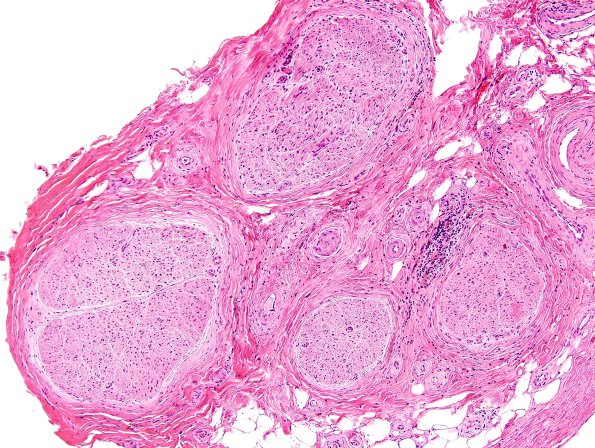

Washington University Experience | PERIPHERAL NEUROPATHY | 7A GUILLAIN-BARRE SYNDROME (GBS) | 2A1 GBS (Case 2) H&E 1

Case 2 History ---- The patient is a 73-year-old male with weakness. Per clinical records, the patient has a history of myelofibrosis, and proximal muscle weakness of several weeks duration. The patient had an MRI of the cervical spine that showed leptomeningeal enhancement of the spinal cord from C2 to C4 concerning for leptomeningeal metastasis, carcinomatosis, and granulomatous disease. Conduction studies showed an axonal sensory motor polyneuropathy. Operative procedure: Right quadriceps muscle biopsy, and right sural nerve biopsy. ---- 2A1,2 Several levels of the sural nerve in this case show epineurial and perineurial inflammation. (H&E)